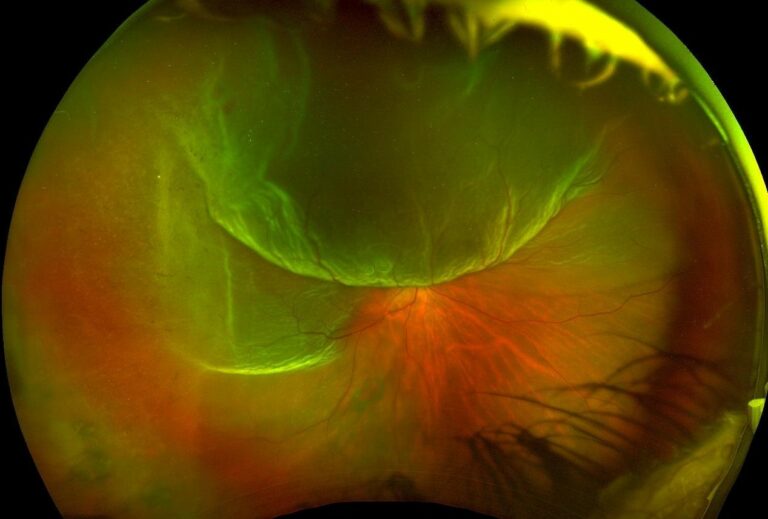

ophtavalmy.frFond D’oeil_Décollement Rétine Supérieur Avec Déchirure Rétinienne

ophtavalmy.frFond D’oeil_Décollement Rétine Supérieur Avec Déchirure Rétinienne